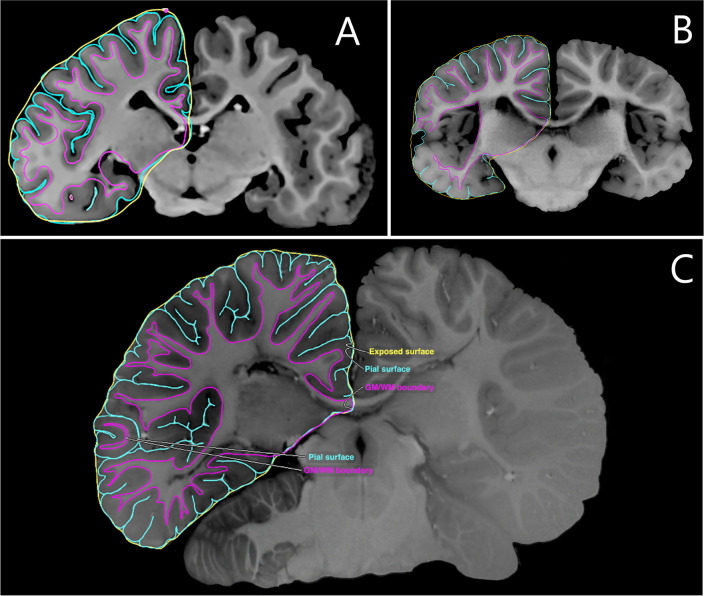

Brain reconstruction, specially of the cerebral cortex, is a challenging task and even more so when it comes to highly gyrified brained animals. Here, we present Stitcher, a novel tool capable of generating such surfaces utilizing MRI data and manual segmentation. Stitcher makes a triangulation between consecutive brain slice segmentations by recursively adding edges that minimize the total length and simultaneously avoid self-intersection. We applied this new method to build the cortical surfaces of two dolphins: Guiana dolphin (Sotalia guianensis), Franciscana dolphin (Pontoporia blainvillei); and one pinniped: Steller sea lion (Eumetopias jubatus). Specifically in the case of P. blainvillei, two reconstructions at two different resolutions were made. Additionally, we also performed reconstructions for sub and non-cortical structures of Guiana dolphin. All our cortical mesh results show remarkable resemblance with the real anatomy of the brains, except P. blainvillei with low-resolution data. Sub and non-cortical meshes were also properly reconstructed and the spatial positioning of structures was preserved with respect to S. guianensis cerebral cortex. In a comparative perspective between methods, Stitcher presents compatible results for volumetric measurements when contrasted with other anatomical standard tools. In this way, Stitcher seems to be a viable pipeline for new neuroanatomical analysis, enhancing visualization and descriptions of non-primates species, and broadening the scope of compared neuroanatomy.